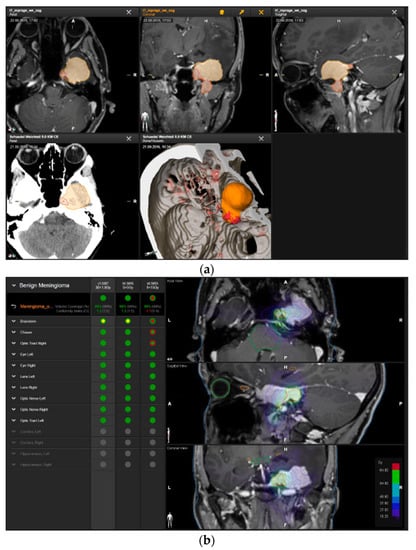

Figure 3.

First representative case with AHSA-assisted tumor resection. (a) Preoperative MRI imaging of tumor (orange) and planned residual tumor volume (red). (b) Dose constraints in the AHSA software for conventional, hypofractionated radiotherapy, and radiosurgery planning for the preoperatively defined residual tumor volume. With this plan, conventional fractionated and hypofractionated radiotherapy were feasible, with effective tumor coverage.

—brainstem: max. dose is marginally safe, whereas mean dose is safe. For single fraction stereotactic radiosurgery, the tumor volume coverage seems effective, while the conformity index was indicating over-treatment.

—brainstem: mean dose is safe, while max. dose is unsafe;

—chiasm: mean dose is unsafe, while max. dose is safe;

—right optic tract: mean dose is unsafe, while max. dose is safe. (c) First intraoperative structure update (ISU) at the time point of 65% residual tumor volume, showing the tumor coverage and organ at risk constraints. At this stage of the resection, AHSA demonstrated that only conventional and hypofractionated radiotherapy were feasible.

—brainstem: max. dose is marginally safe, whereas mean dose is safe. (d) Second ISU acquisition and residual tumor reduction to 58%. (e) Third ISU acquisition with a reduction of residual tumor volume to 41%. Dose constraints for conventional, hypofractionated radiotherapy, and radiosurgery are demonstrated. At the final stage of the resection, the conventional and hypofractionated radiotherapy organ risk constraints were unchanged.

—brainstem shows that max. dose is marginally safe, whereas mean dose is safe. The single-dose stereotactic radiosurgery constraints show that:

—brainstem: mean dose safe, max. dose unsafe;

—chiasm: mean dose unsafe, max. dose safe;

—right optic tract: mean dose marginally safe, max. dose unsafe. (f) Fusion of intraoperative CT to final intraoperative ISU. (g) Preoperative and 3 months postoperative MRI imaging for planning of radiosurgery (5 × 5 Gy).